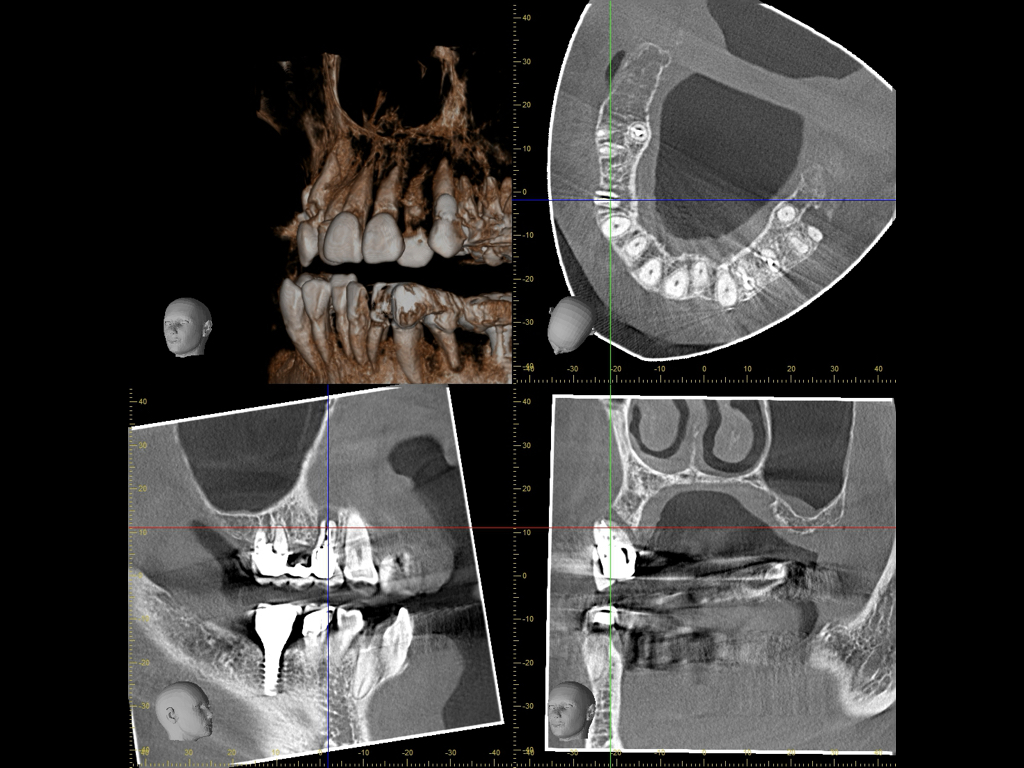

歯科用CTについて